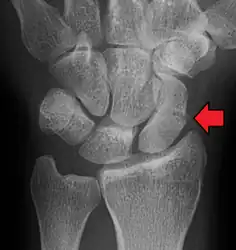

A subtle scaphoid fracture